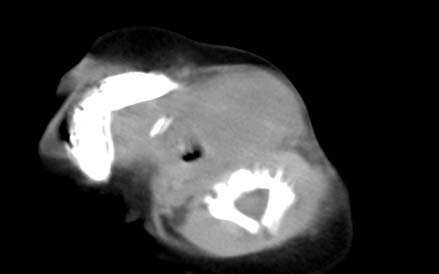

男,26天,发现左侧颈部包块5天,质较硬,患儿不哭不吵,无明显发热,头向右侧歪斜,其父母诉患儿出生时正常,昨天查血象wbc19.4×10的9次方/l,b超考虑来源于甲状腺的恶性肿瘤,我科认为肿块内有低密度区,而且病程发展较快,血象高,考虑炎性病变可能大。患儿年龄太小没做增强。请大家提出高见。

男,26天,发现左侧颈部包块5天,质较硬,患儿不哭不吵,无明显发热,头向右侧歪斜,其父母诉患儿出生时正常,昨天查血象wbc19.4×10的9次方/l,b超考虑来源于甲状腺的恶性肿瘤,我科认为肿块内有低密度区,而且病程发展较快,应该首先排除血肿,其次考虑感染

随访结果:炎症(患儿经过一星期抗炎治疗后颈部包块明显缩小,现已经正常)。